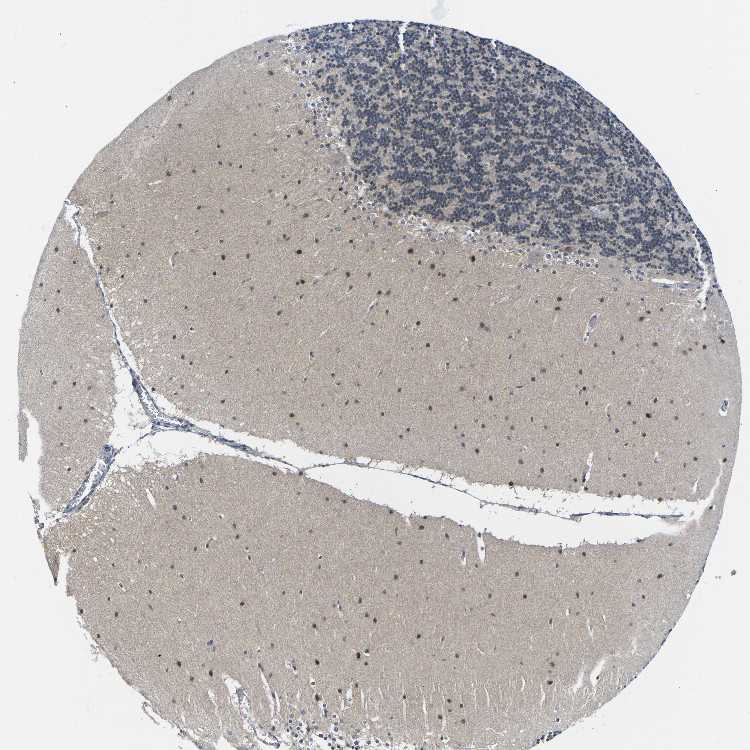

CEREBELLUM - Antibody stainingi

Antibody staining in the annotated cell types in the current human tissue is reported as not detected, low, medium, or high, based on conventional immunohistochemistry profiling in selected tissues. This score is based on the combination of the staining intensity and fraction of stained cells.

Each image is clickable and will lead to virtual microscopy that enables deeper exploration of all samples and also displays staining intensity scores, fraction scores and subcellular localization as well as patient and tissue information for each sample.

Antibody CAB015444

Purkinje cells Low

Cells in granular layer Medium

Cells in molecular layer High